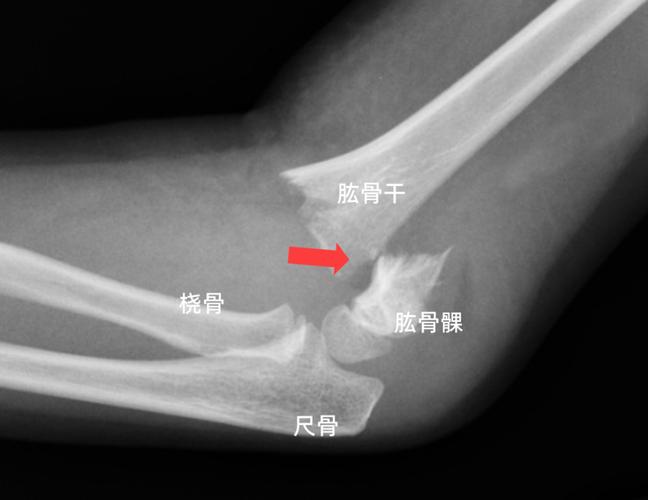

肱骨干与肱骨髁

肱骨干与肱骨髁,肱骨髁间骨折

肱骨近折端向后下移位,远折端向前移位,为屈曲型肱骨髁上骨折的表现.